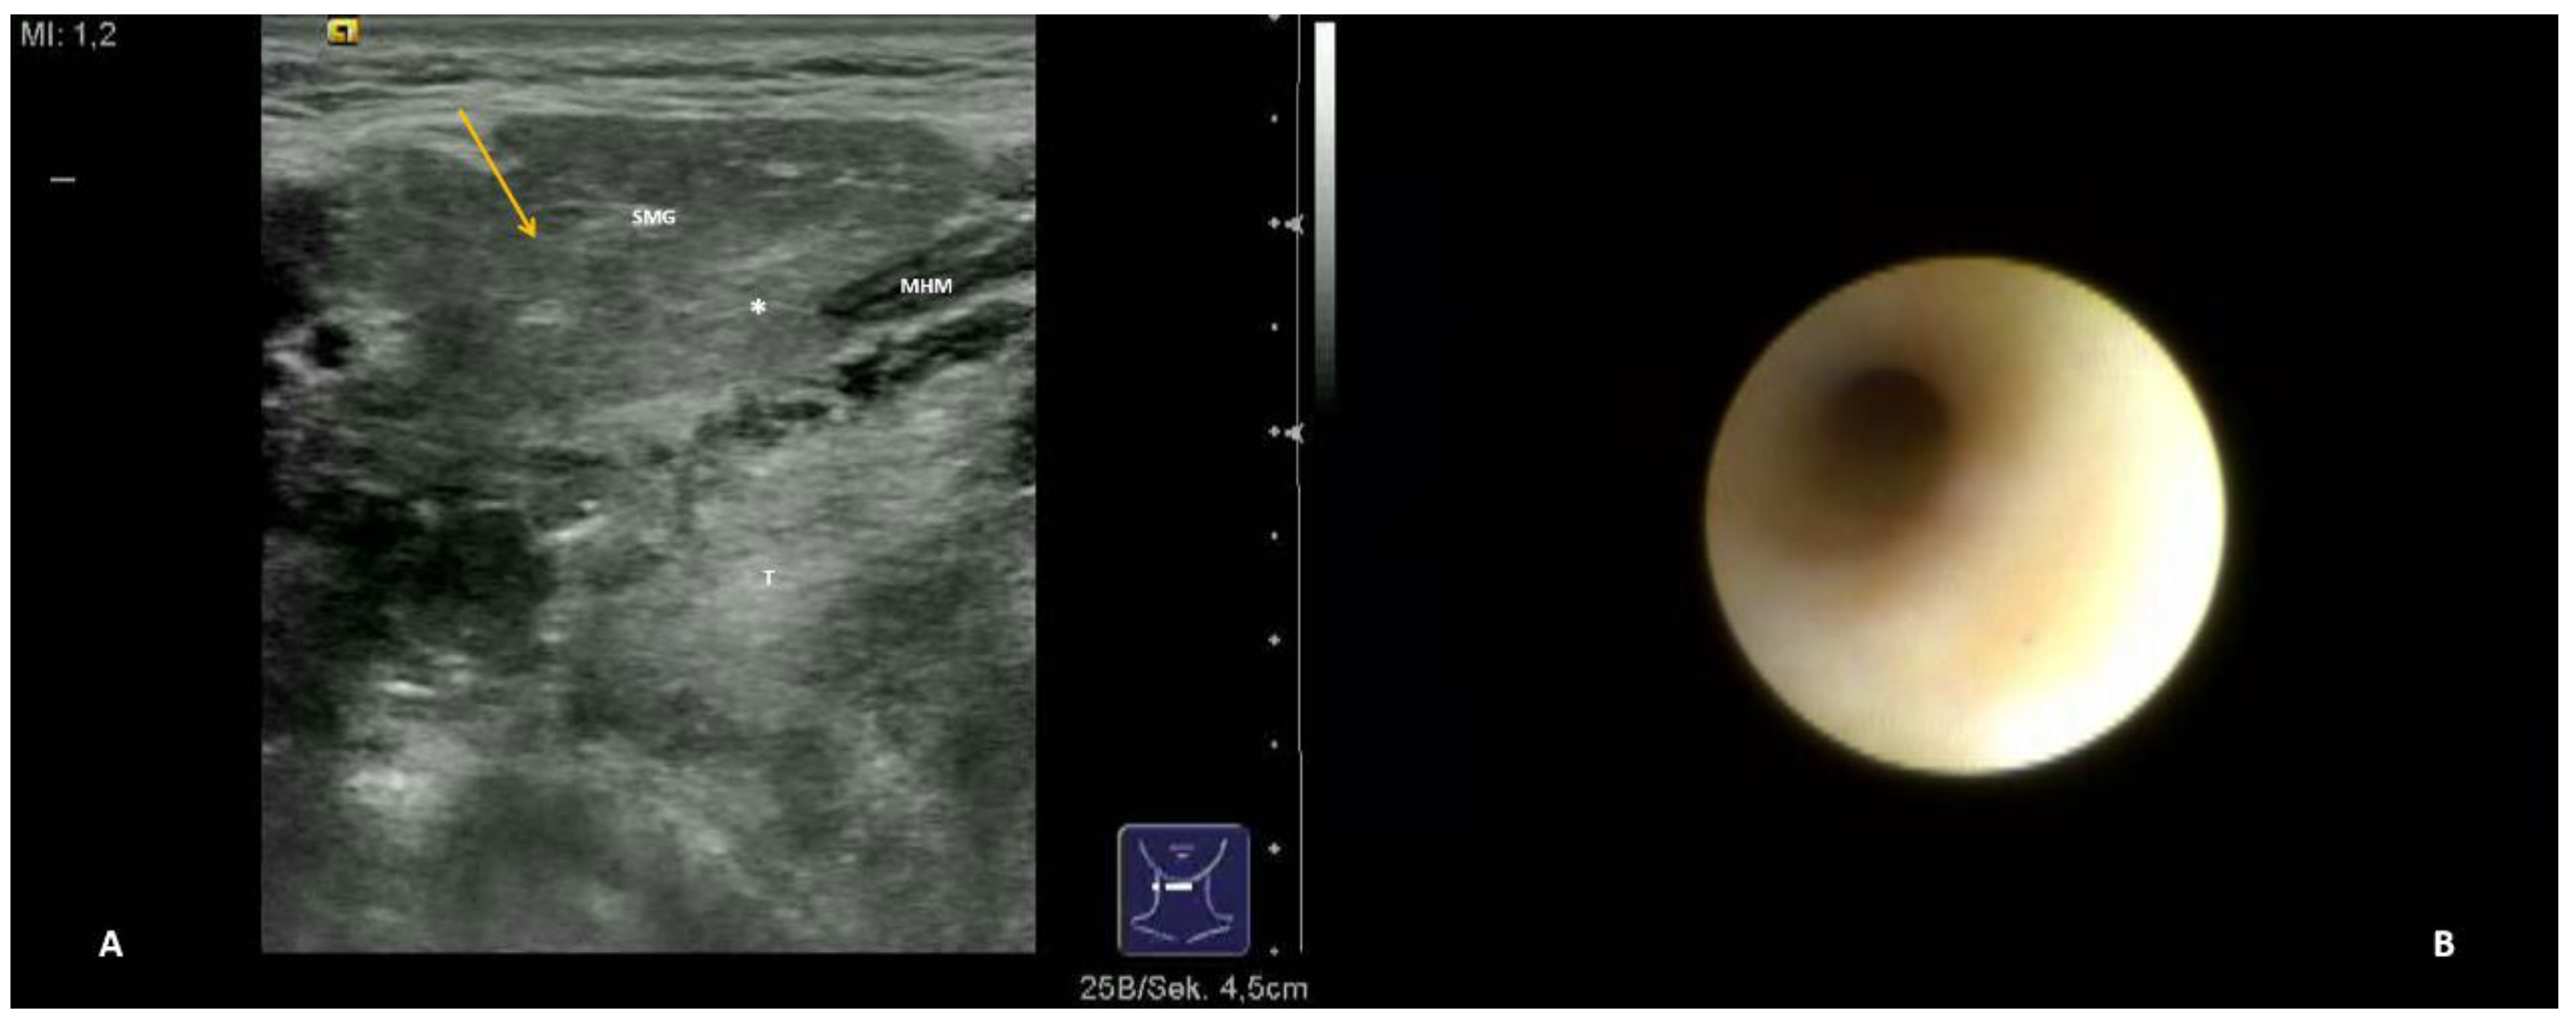

- Long duct stenosis (≥3 cm; Figure 4B; Supplementary Video S4)